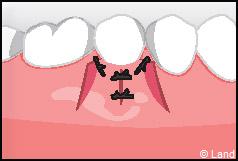

LES TECHNIQUES AVEC APPORT DE GENCIVE OU « GREFFE DE GENCIVE » :

Elles font appel à un prélèvement sur le patient à un endroit où elle est en excès, qui est ensuite posé sur la récession.

Les greffes épithélio-conjonctives :

Elles sont pratiquées pour des zones non esthétiques de la cavité buccale, à cause de l’aspect « rustine» que la cicatrisation leur confère.

Destinées aux zones esthétiques, elles consistent à prélever la partie profonde du palais (site donneur).